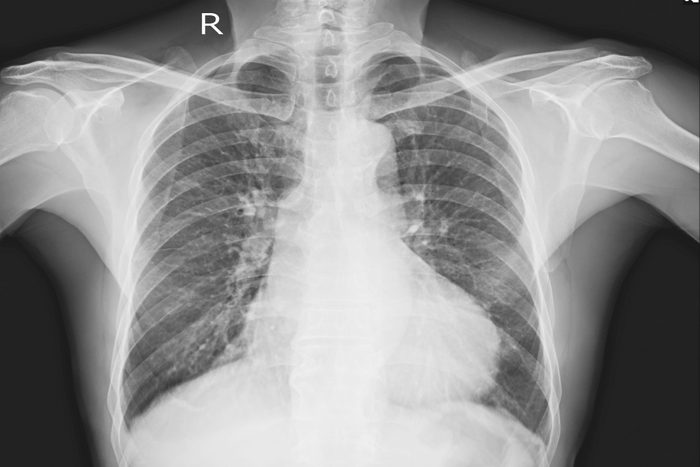

Cancer

Another source of shoulder pain could also be cancer—most often, lung cancer. According to a 2015 study, 14 percent of people with mesothelioma (which is usually due to asbestos exposure) reported shoulder pain, and it was often the first symptom. A couple of other types of lung cancer may also cause shoulder pain: Pancoast tumors, which are located in the upper lungs, and metastatic lung cancer. The tricky thing about lung-cancer–related shoulder pain—called “referred pain” because it starts elsewhere in the body—is that it may not be severe and it can be mistaken for arthritis. Other telltale signs that cancer is the cause can be a chronic cough that sometimes produces blood, labored breathing, fatigue, unexplained weight loss, and recurrent respiratory infections.